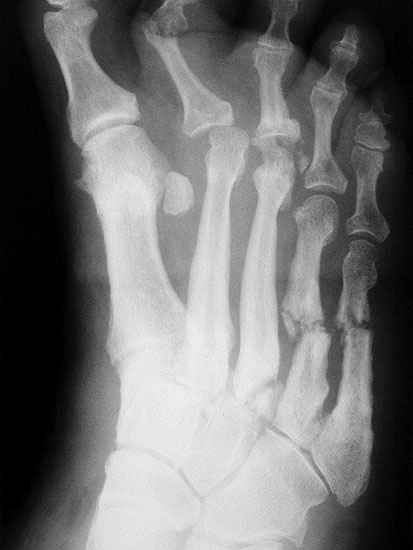

Abbildung 3

DNOAP Typ II (Abb. 3)

Typ II der DNOAP betrifft die Tarsometatarsalgelenke. Hierbei kommt es zur Ausbildung eines hochgradigen Plattfußes durch Luxation der Ossa cuneiformia und/oder naviculare. Typische Folge ist eine ausgeprägte Vorfußabduktion. Durch die hohe Druckbelastung im cuneiforme-naviculare Bezirk sind plantare Ulcerationen häufige Folge.